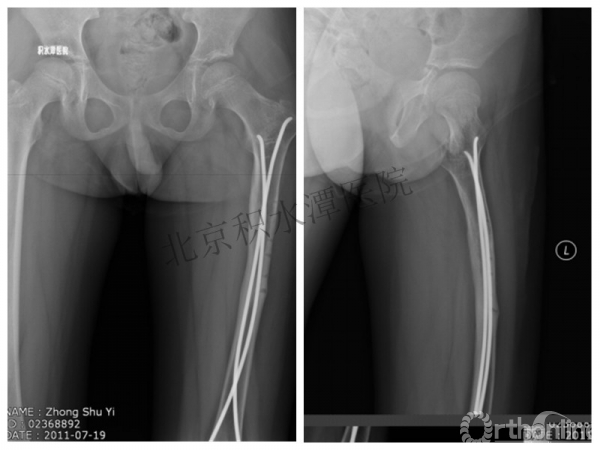

整整11年!是否治疗终结?

病人的付出?医生当反思!

一、思考

1.使用了医生可以使用的所有固定方式

2.似乎哪一次的处理都没有违背原则

3.问题出在哪儿?

4.骨折治疗—手术不是万能的!